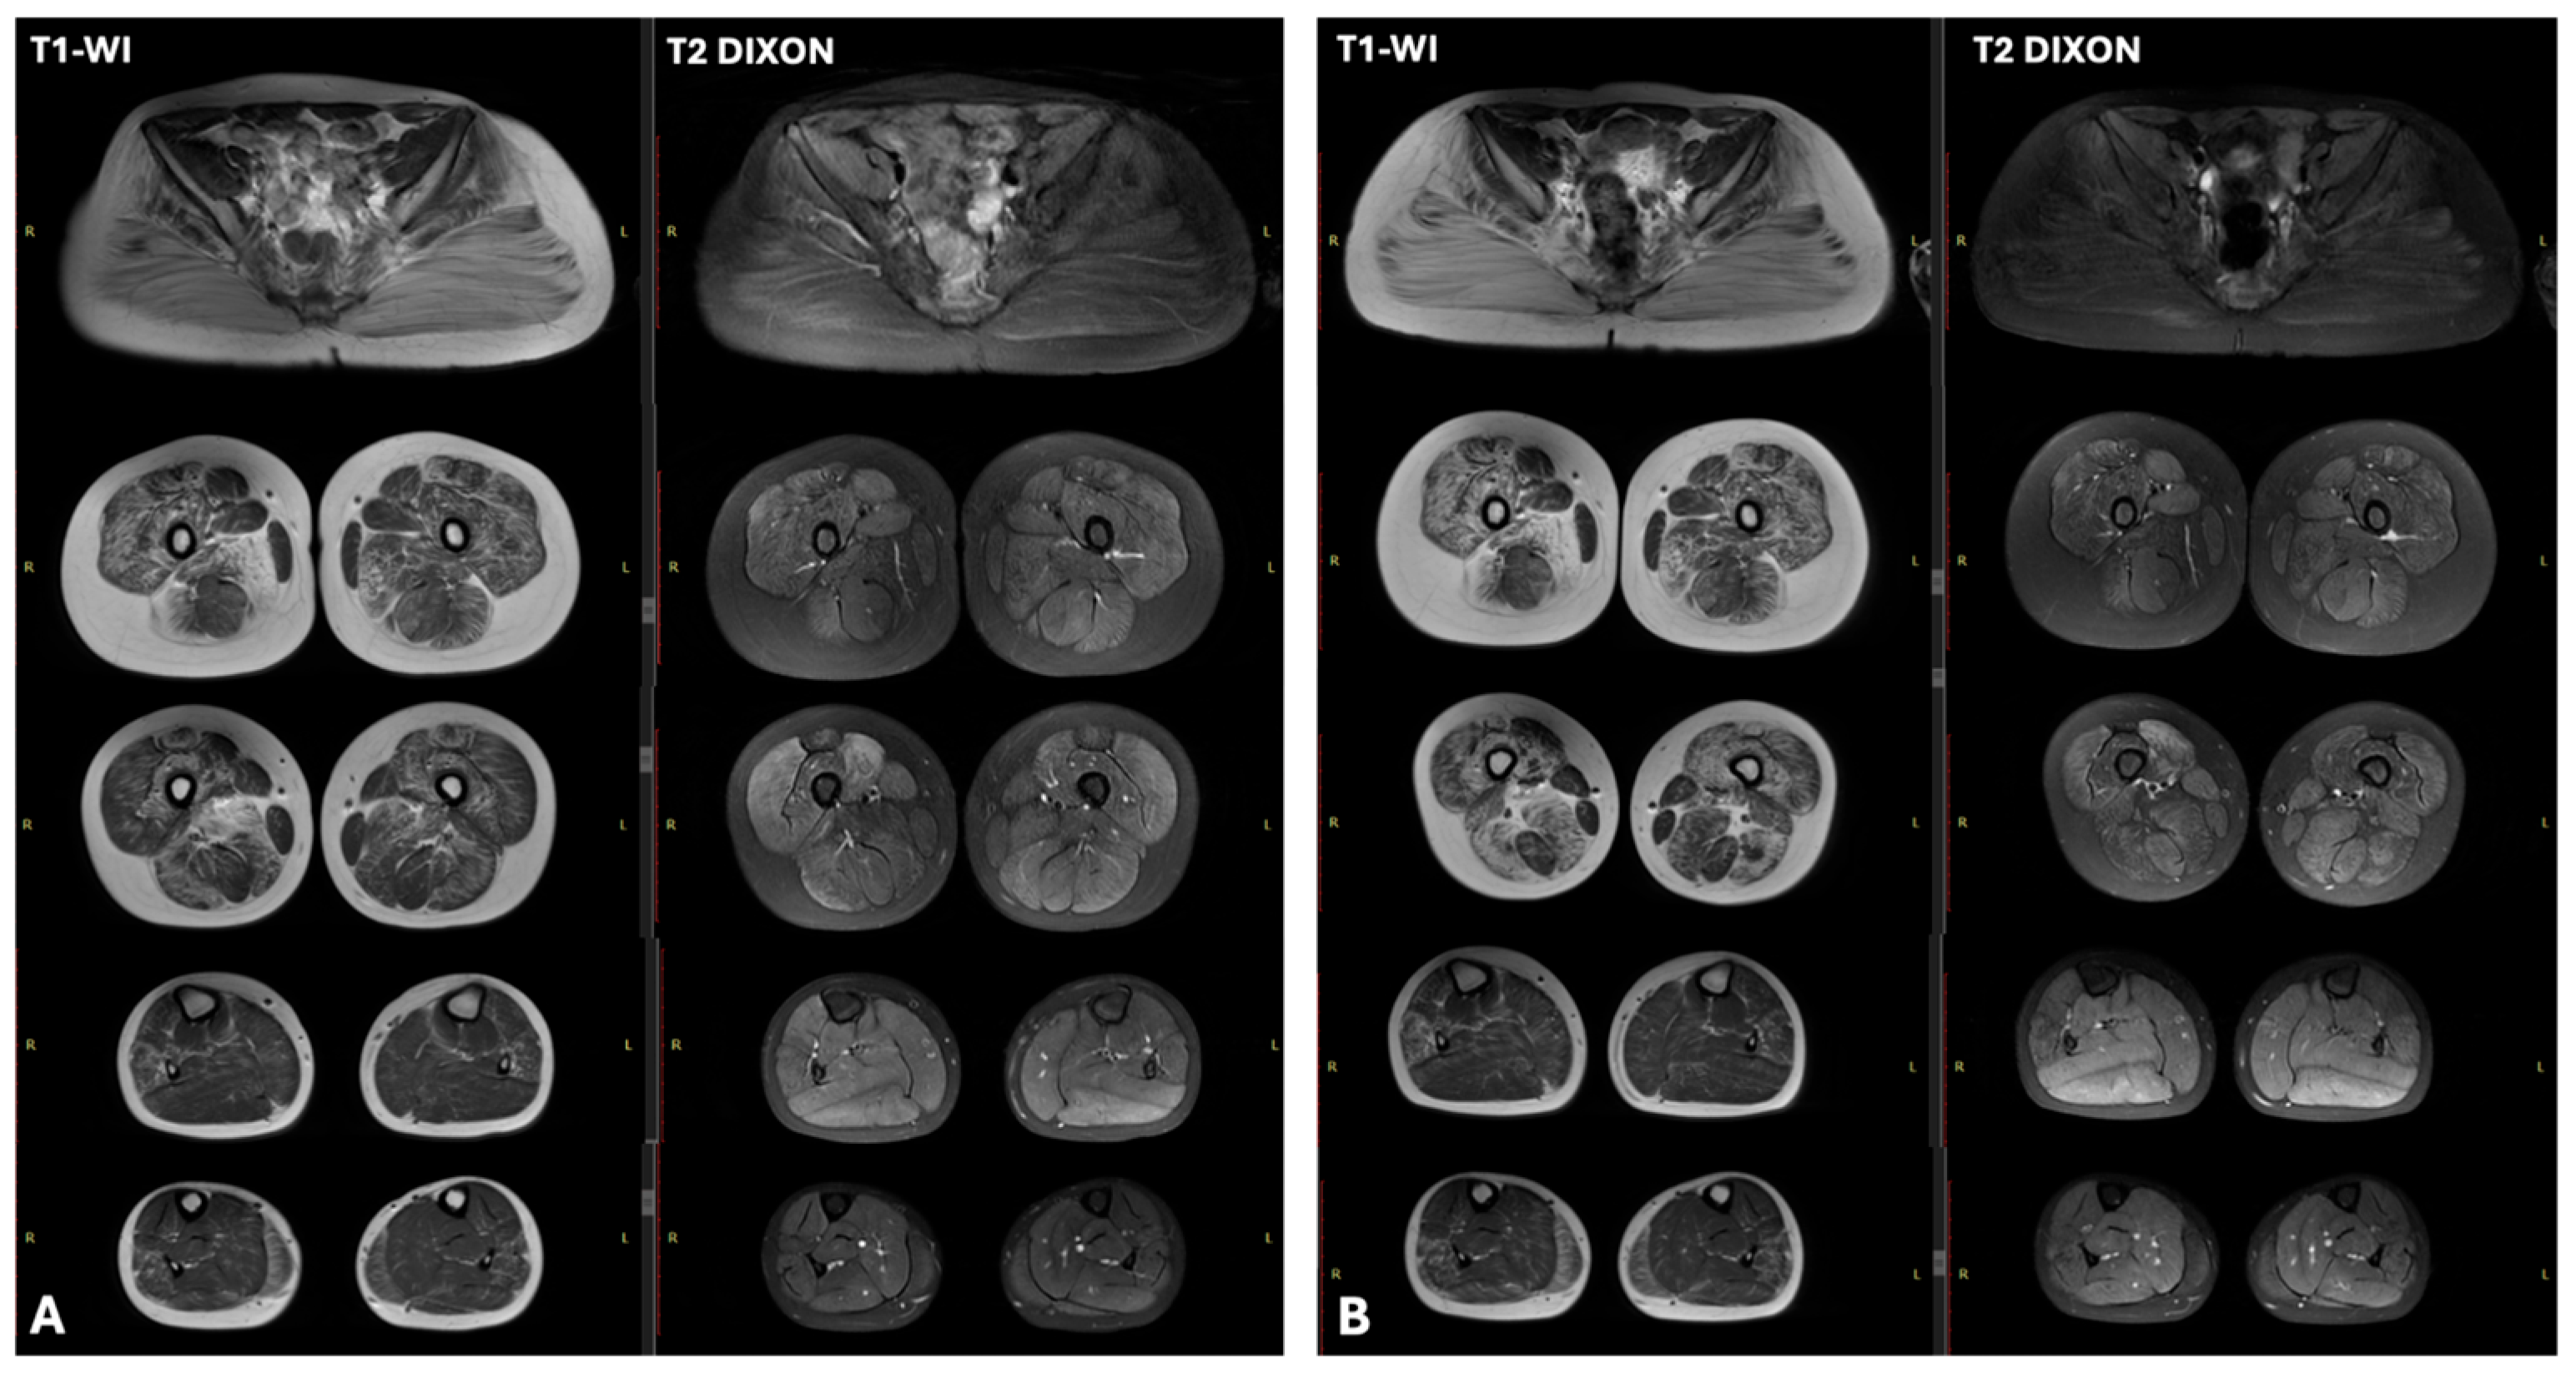

| Patient | CK (U/L) | ALT and AST (U/L) | ECG | Cardiac US | Lower Limb Muscle MRI | EMG |

|---|---|---|---|---|---|---|

| N1 | 26,694 | x11 | Moderate sinus arrhythmia, incomplete RBBB. Deep Q wave in leads III and aVF. Slight impairment of repolarization in the myocardium, manifested as T wave flattening in lead III | LVEF—61.4% (normal >60%), LVEDD—37.4 mm (normal <37 mm). | T1-WI showed no fatty infiltration. T2 DIXON images revealed clear hyperintensity within the soleus and medial gastrocnemius muscles | myogenic pattern |

| N3 | 16,000 | x3–5 | Abnormal ventricular repolarization | No changes | Characteristic “trefoil with a single fruit” sign, with severe involvement of the adductor magnus and biceps femoris and relative sparing of the gracilis, sartorius, adductor longus, and semitendinosus. | myogenic pattern |